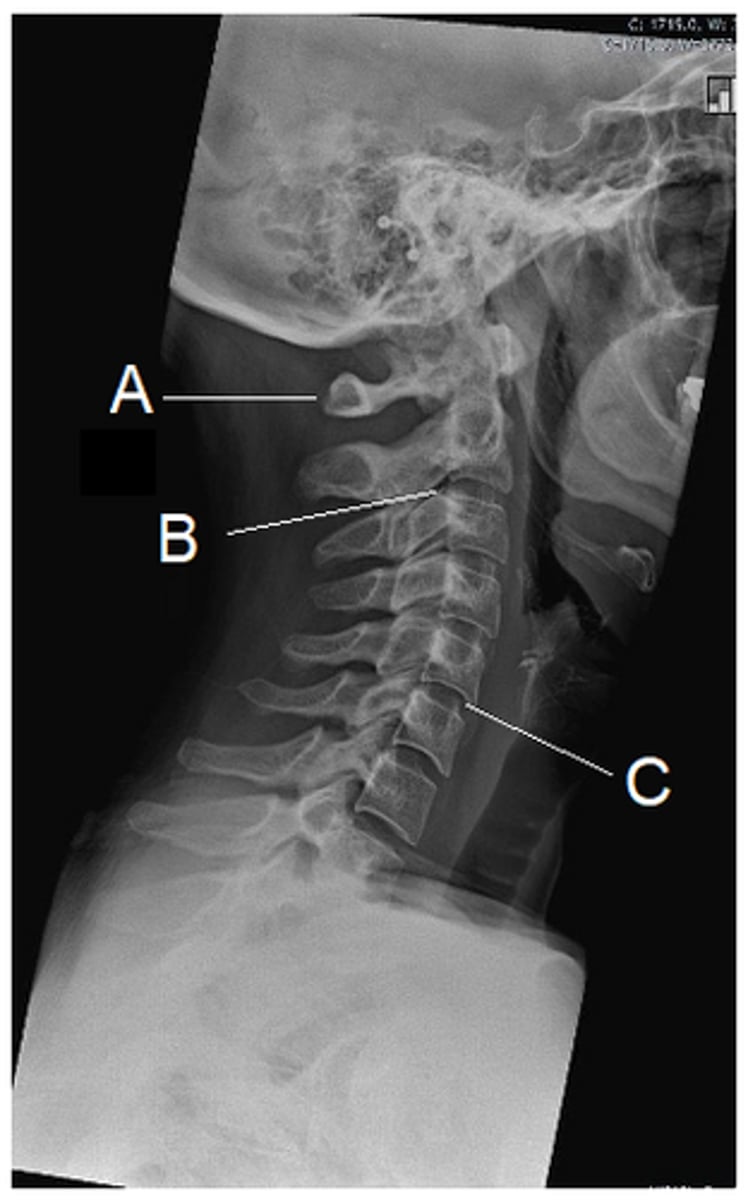

What does 'B' represent?

intervertebral disk

In the image, 'B' represents:

Zygapopgyseal joint

In the image, 'C' represents:

Intervertebral foramen (C5-6)